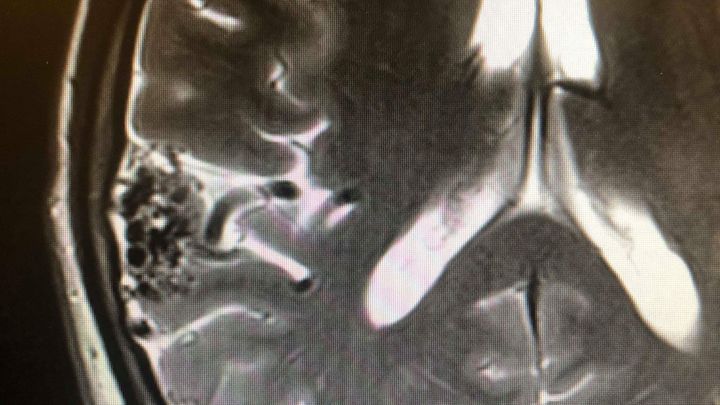

Hello, my name is Jordan. In October 2018, after suffering with headaches and chronic pain for most of my life, my girlfriend finally convinced me to go and see a doctor. I was sent for a scan on the 7th and by the 8th I received a phone call telling me I had a brain condition called an Arteriovenous Malformation (my brain scan below). Said brain condition can cause things such as bleeds on my brain, strokes, brain damage and death. With this condition, and symptoms such as chronic pain and fatigue, I can no longer work. I'm currently waiting on a number of tests/treatments, but all require me to be admitted to hospital. This means as much as would like to get a job and soldier through, no employers will keep me on with how much time I require off. I would like to ask for your help to raise some money so I can do things such as food shopping, travel to and from the hospital (I'm unable to drive and I'm not eligible for patient transport) and prescriptions. Anything you are able to give would greatly help reduce the stress my financial situation is having on me, and I'll be able to focus on the treatments. My plea is urgent and desperate so anything you can give would be most appreciated.